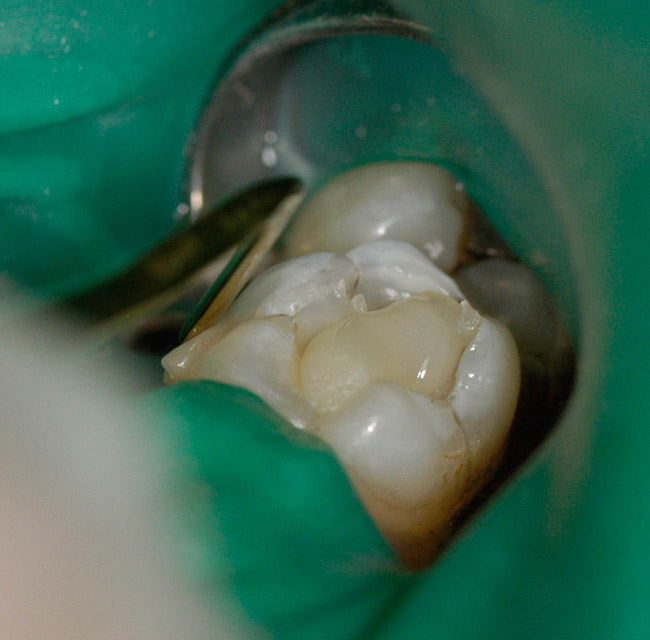

Contemporary resin-based composites have addressed the many problems they have experienced since their introduction. Fillers have made them stronger, more resistant to wear, and increased their polishability. Fillers have also reduced the stress induced during photopolymerization.22 Although shrinkage on photopolymerization has been decreased, it still remains a significant problem with Class 1 restorations on posterior teeth23 (Figure 1).

Figure 1   Two posterior molars with marginal failure and recurrent decay.

Figure 1